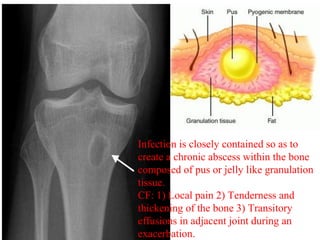

Infection is closely contained so as to

create a chronic abscess within the bone

composed of pus or jelly like granulation

tissue.

CF: 1) Local pain 2) Tenderness and

thickening of the bone 3) Transitory

effusions in adjacent joint during an

exacerbation.

Infection is closelycontained so as to create a chronic abscess within the bone composed of pus or jelly like granulation tissue. CF: 1) Local pain 2) Tenderness and thickening of the bone 3) Transitory effusions in adjacent joint during an exacerbation.